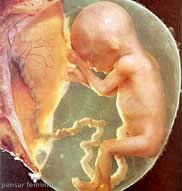

- Com 16ª semanas de gestação, o bebê não cabe mais na tela como antes. Agora ele tem que ser visto no ultrassom por partes.

Com 16 semanas de gestação, você está no final do 4º mês gestacional. O bebê não cabe mais na tela como antes, agora ele tem que ser visto no ultrassom por partes. E agora sim o médico já pode falar para você se o seu mundo é rosa ou azul! Um truque válido é comer chocolate 30 minutos antes do ultrassom. Assim seu bebê ficará ativo e a probabilidade de abrir as perninhas aumenta muito.

Com 16 semanas de gravidez, suas medidas podem chegar a 11,6 cm e 100 gramas. Como cresce rápido! Já está completamente formado, e apenas está crescendo e ficando forte para o nascimento. Lembre-se: o pré-natal é muito importante para você, mas principalmente para o seu bebê1! Se ainda não começou a fazer, já passou da hora!

As 16 semanas de gravidez marcam o quarto mês de gestação. Suas pálpebras ainda se encontram fechadas, porém já possui certa sensibilidade à luz. Seu ouvido interno já está totalmente formado e agora já começa a ouvir sons2. Em breve conseguirá reconhecer as vozes do papai, da mamãe e dos familiares mais próximos e responder a estímulos.

Nesta fase suas sobrancelhas começam a aparecer e seus lábios ganham o contorno bem nítido. Seus músculos já estão formados e totalmente ativos. Sua pele tem cor rosada e é tão fina que é possível enxergar todas suas veias e vasos sanguíneos